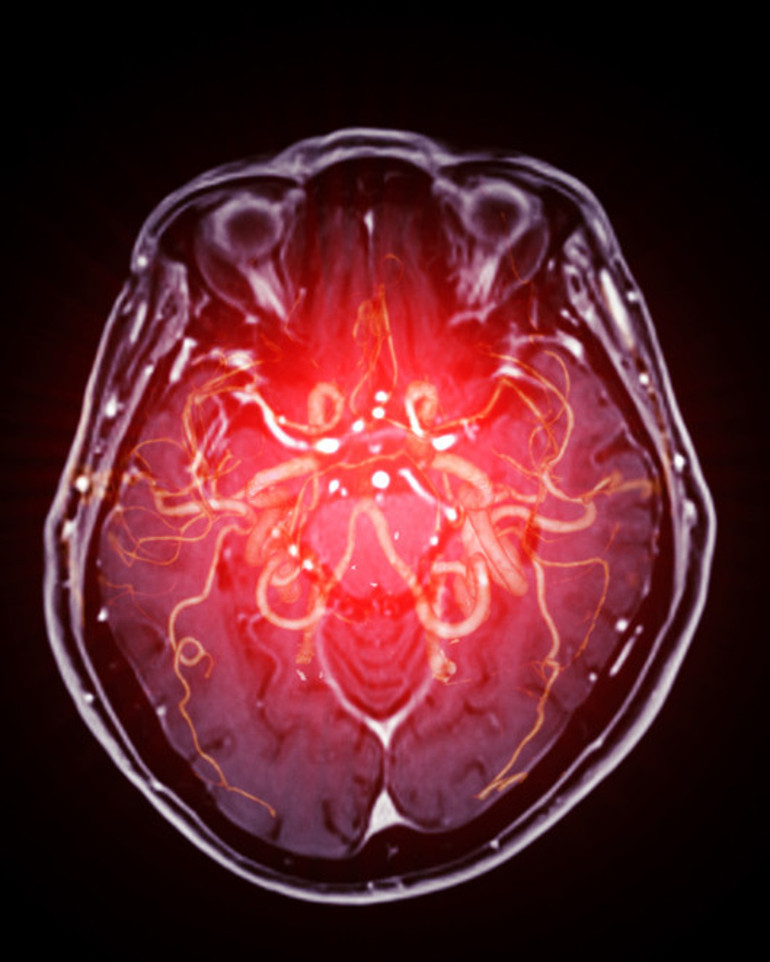

Bilgisayarlı Tomografi taramasında beyin kanaması tespit edilince acilen helikopterle Brisbane'deki yoğun bakım ünitesine kaldırıldı.

Kaynak: Daily Mailİnme, beyne giden kan akışının kesilmesi ve beyin hücrelerinin ölmesiyle meydana gelir. Hasar uzun süreli sakatlığa yol açabilir ve insanların düşünme ve hissetme biçimlerini etkileyebilir.En yaygın neden, iskemik inme olarak bilinen beyni besleyen arterleri tıkayan yağ birikintileri veya kan pıhtısıdır. Bu, kan damarlarının zamanla plaklar tarafından daraltıldığı veya tıkandığı kardiyovasküler hastalık nedeniyle olur. Bunlar, ateroskleroz olarak bilinen bir süreçte arter duvarlarında biriken kolesterol, kalsiyum ve diğer maddelerden oluşur.

Hemorajik inme olarak adlandırılan diğer atak türü ise beyinde bir kan damarı hasar aldığında ve kanı organa sızdırmaya başladığında meydana gelir.